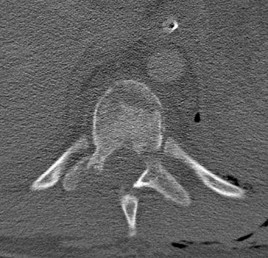

A 35-year-old male construction worker falls 10 feet from scaffolding. He complains of moderate low back pain but has full strength and normal sensation in his lower extremities.

CT imaging shows an L1 burst fracture with 40% loss of anterior vertebral body height and 50% retropulsion into the spinal canal. MRI confirms that the posterior ligamentous complex (PLC) is intact. Based on the Thoracolumbar Injury Classification and Severity (TLICS) score, what is the appropriate score and recommended management?